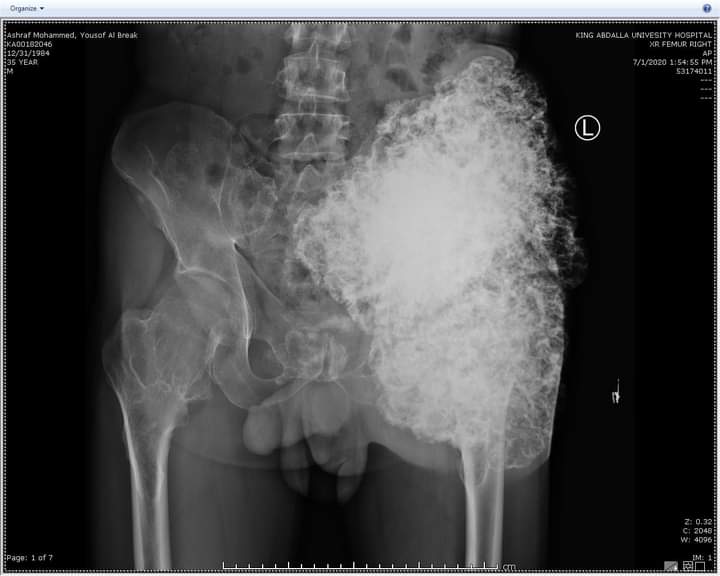

تمكن قسم الجراحة الخاصة / شعبة العظام في مستشفى الملك المؤسس عبدالله الجامعي  من إجراء عملية نوعية لمريض ثلاثيني يعاني من ورم عظمي ضخم داخل تجويف الحوض ملاصق للأوعية الدموية والأوردة الرئيسية والأعصاب يزن قرابة (٥) كيلو غرامات يقع في منطقة ضيقة من منطقة الحوض الداخلية  بجانب تجويف البطن والأمعاء حيث ان هذه المنطقة يصعب الوصول اليها لمدى خطورتها .

وأجرى العملية فريق طبي بإشراف إستشاري جراحة أورام العظام  الدكتور زياد مهيدات وأستغرقت العملية الجراحية اربعة ساعات بعد أن تعذر إجراءها في مراكز طبية أخرى و تعتبر هذه العملية من العمليات الصعبة والمعقدة  حيث أظهرت الفحوصات والأشعة التي أجريت للمريض وجود ورم عظمي ضخم داخل تجويف الحوض من الجهة الداخلية الى خارج الجسم مع وجود إحتمالية تحوله الى ورم خبيث في أي لحظه حيث كان لزاماً ازالته مبيناً إن هذه العمليات يجريها بالعادة فريق جراحين متخصصين في مراكز متخصصة مثل هذا المركز الجامعي المميز والمجهز بأحدث الأجهزة والذي يشهد تقدماً كبيراً .